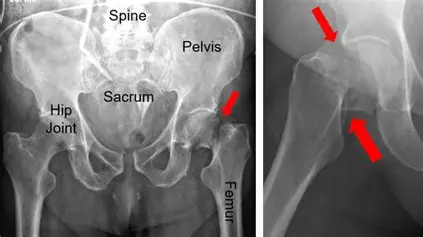

Neck Of Femur Fracture (NOFF)

“NOFF” typically stands for Neck of Femur Fracture, which is a type of hip fracture—a serious injury, especially common in older adults. It usually occurs in the upper part of the thigh bone (femur), just below the ball of the hip joint.

Why it matters:

- High risk in the elderly: Often caused by falls, especially in people with osteoporosis.

- Serious complications: Can lead to reduced mobility, long-term care needs, and even increased mortality if not treated promptly.

- Surgical treatment: Most cases require surgery—either fixation with screws/pins or hip replacement.

Symptoms

- Severe hip or groin pain, especially after a fall

- Inability to stand or walk on the affected leg

- Shortened and externally rotated leg (the foot points outward)

- Swelling or bruising around the hip area

- Pain on gentle movement of the leg

In Older Adults

- They may not always report pain clearly—look for:

- Confusion or agitation (delirium can be the first sign)

- Reluctance to move or bear weight

- Limping or dragging the leg